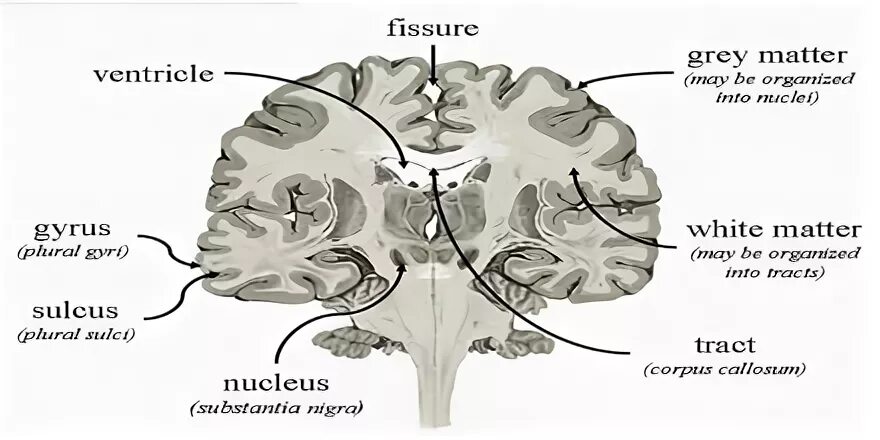

Grey matter